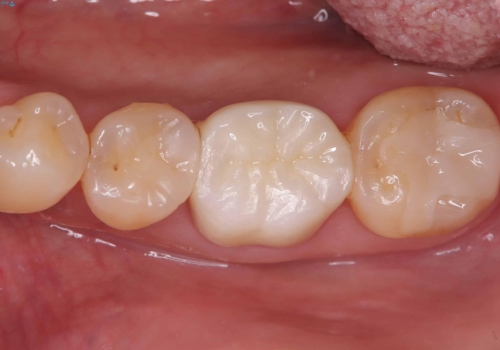

根管の中が空洞のままで被せ物と歯のきわも合っておらず適合が悪い状態でした。根尖部付近にはパーフォレーションリペア修復の痕がありました。バイオシーシーラーを使用しシングルポイント法で充填しました。空洞があると細菌が増える環境になってしまうので、根管治療からやり直し、緊密に充填しました。被せ物の見た目も大変満足していただけました。